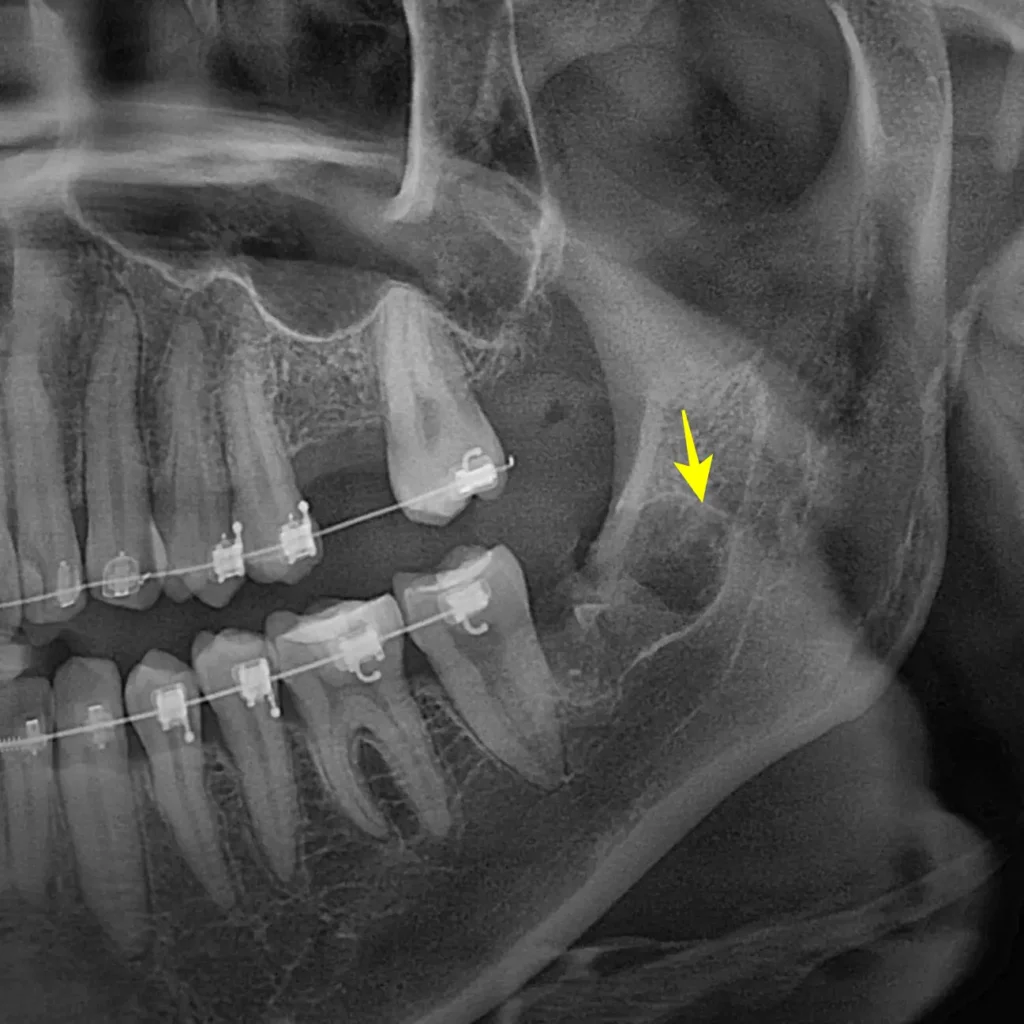

이번에 내원하신 환자분도 타 치과에서 발치가 어렵다는 소견을 듣고 오셨습니다. 사랑니가 신경과 가깝고 뿌리가 휘어진 고난도 케이스였습니다.

STEP 1 정밀 진단 및 계획 수립 먼저 파노라마와 3D CT를 분석합니다. 하치조 신경관과 사랑니 뿌리의 거리를 파악합니다. 이번 경우는 뿌리가 신경 쪽으로 휘어 있어 주의가 필요했습니다.

STEP 3. 치아 분할 및 발치 브라켓과 와이어를 건드리지 않도록 기구를 조심스럽게 진입시킵니다. 잇몸 아래에 숨은 사랑니 머리 부분을 정확하게 분할합니다. 공간을 만든 뒤 뿌리까지 깔끔하게 제거합니다.